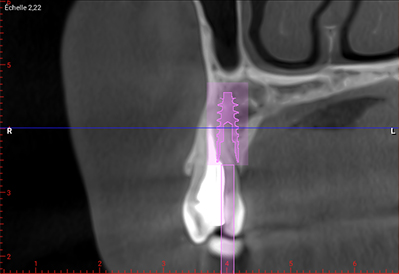

Fig. 03 : CBCT et planification implantaire (Nobel Active 3,5×13).

L’implant doit être placé de manière optimale dans les trois dimensions de l’espace :

• 3 à 4 mm en dessous de la gencive marginale vestibulaire ou de la jonction émail-cément des dents adjacentes ;

• 2 à 3 mm des dents adjacentes dans le respect de l’espace biologique péri-implantaire ;

• 3 à 4 mm à partir du rebord externe de la corticale vestibulaire créant ainsi un hiatus péri-implantaire.